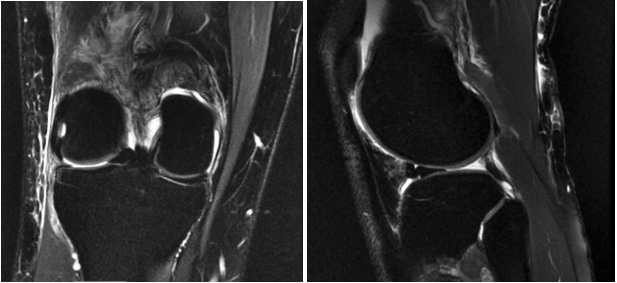

After successful osteopathic manipulative treatment, an MRI was ordered for further evaluation, which was completed in the outpatient setting within the week. MRI revealed a bucket-handle lateral meniscus tear with an associated large joint effusion (refer below). No additional ligament tear or chondral displacement was seen.

Due to staffing limitations, we could not obtain an MRI in the acute setting. An MRI was obtained in the outpatient setting 6 days after the patient’s presentation to the emergency department and successful “unlocking” of the knee. Therefore, we can only ascertain from a close follow-up MRI that the locked knee presentation was due to a bucket-handle meniscus tear.